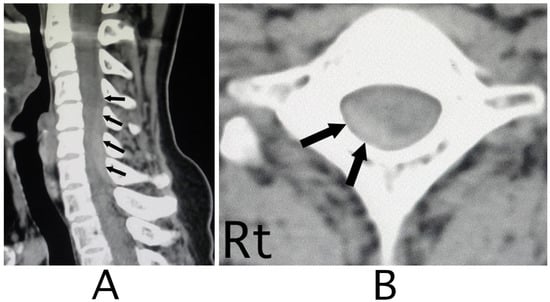

The lesion in the intracranial region or the cervical spinal cord was suspected. Computed tomography (CT) images of the head and X-ray of the cervical bone were normal; however, sagittal CT images of the cervical bone showed a slightly abnormal high-density area (HDA) behind the spinal cord at the level between C4 and C7 (Figure 3A). This abnormal HDA was located in the posterior part on the right side in axial CT images (Figure 3B). MRI analysis was performed because the presence of a hemorrhagic lesion was suspected, based on the CT findings of the cervical bone. Sagittal T1-weighted MRI showed an iso-intensity mass in the epidural space behind the spinal cord at the level from C4 to C7 (Figure 4A). The lesion was noted as a heterogeneous high-intensity mass in sagittal T1-weighted images (Figure 4B). Axial T1-weighted MRI showed an iso-intensity mass in the posterior part on the right side in the epidural space and mild compression of the spinal cord (Figure 5A). The lesion was noted as a heterogeneous high-intensity mass in axial T2-weighted images (Figure 5B).

Figure 3. CT images of the cervical bone. CT images of the sagittal position showed a slight high-density mass behind the spinal cord at the level between C4 and C7 (black arrows) (A). The mass was located diagonally posterior part on the right side (black arrows) (B). (Rt = right).